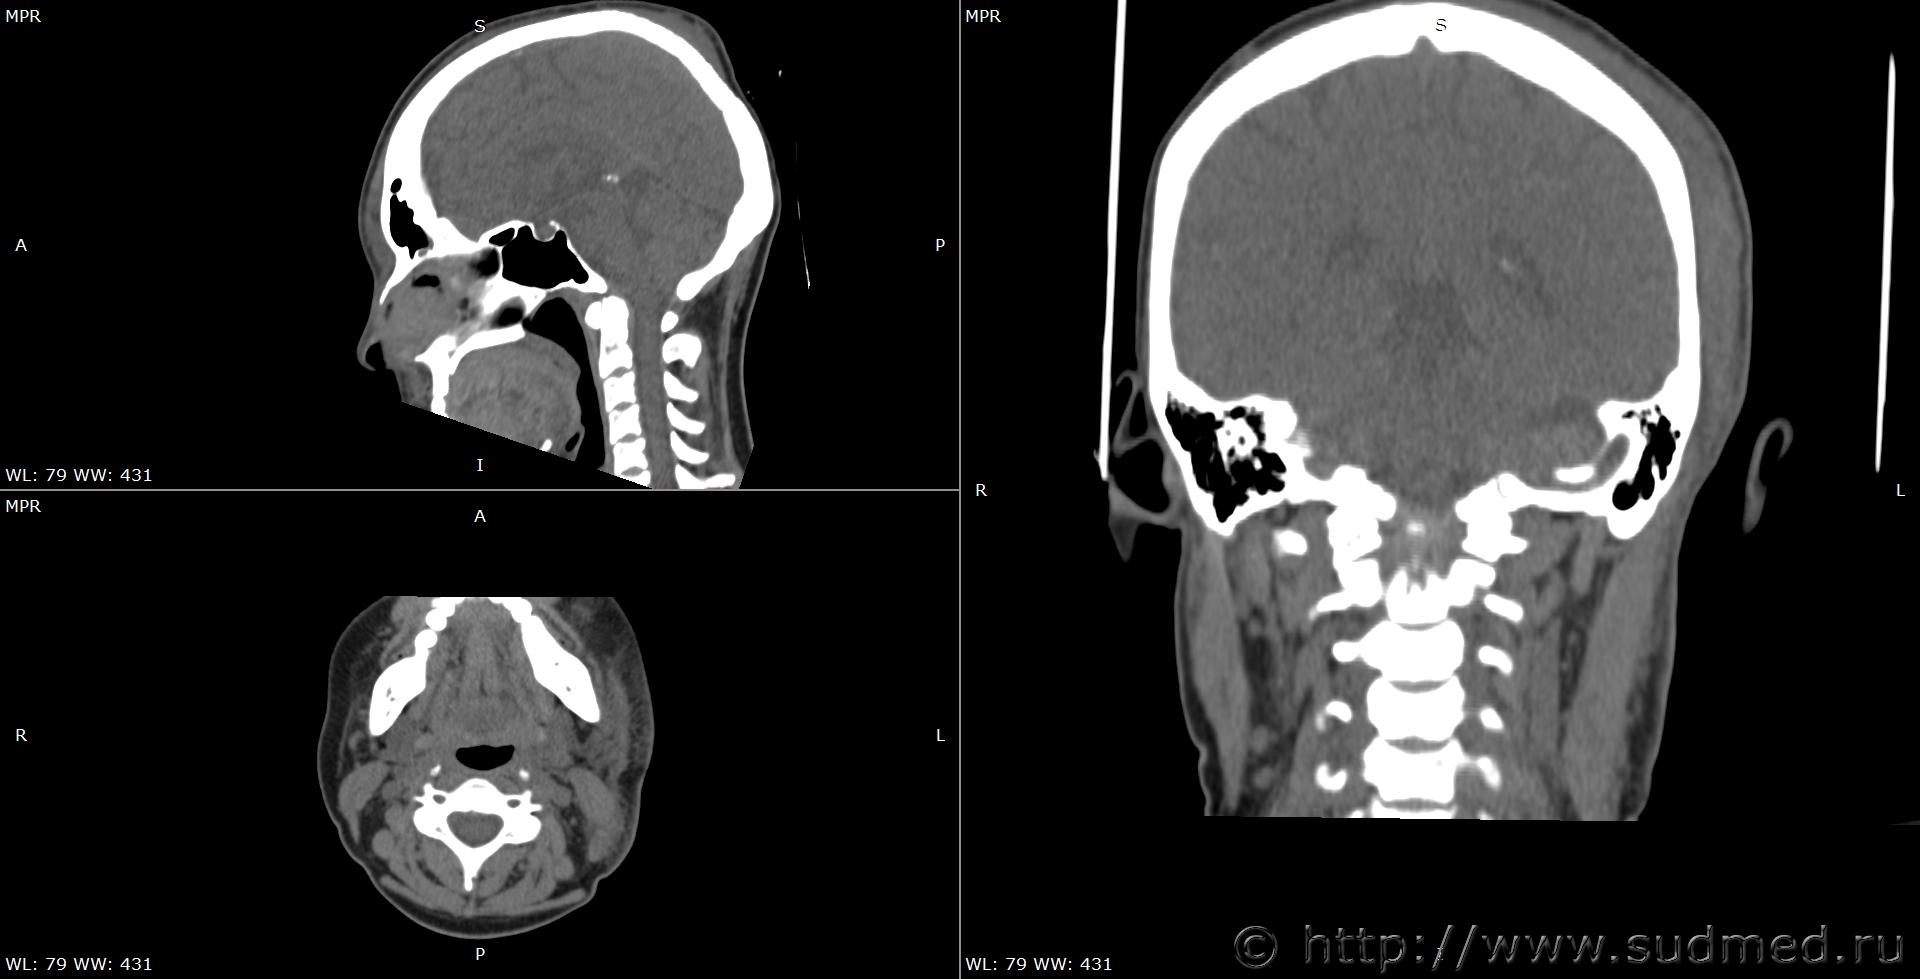

При экспертизе живого лица по медицинским документам встретились переломы шиловидных отростков височных костей. Женщина 39 лет, обратилась за медицинской помощью на 5-е сутки после травмы, тогда же провели РКТ. До этого никуда не обращалась. В протоколе РКТ отметили перелом шиловидного отростка левой височной кости, на снимках перелом на границе верхней и средней трети, дистальный отломок слегка смещен кпереди, каких-либо признаков заживления нет. Длина отростка 2,19 см. Судебная медицина - Прикрепленное изображение Также на КТ визуализируется перелом шиловидного отростка правой височной кости в нижней трети с выраженным смещением, думаю, отрывного характера (его длина 2,01 см), также без каких-либо признаков заживления Судебная медицина - Прикрепленное изображение; и гематома теменной области слева с переходом, в частности, на левую височную область, область левого сосцевидного отростка, левые околоушно-жевательную и скуловую области, левую боковую поверхность шеи Судебная медицина - Прикрепленное изображение, увеличение в объеме, нечеткость контура и разволокнение левой грудино-ключично-сосцевидной мышцы и левой ременной мышцы головы в верхней трети Судебная медицина - Прикрепленное изображение, вокруг них, в том числе кнутри от ременной мышцы, повышение плотности ПЖК Судебная медицина - Прикрепленное изображение; такие же изменения плюс повышение плотности левой подкожной мышцы шеи Судебная медицина - Прикрепленное изображение, увеличение в объеме и нечеткость контура левой околоушной слюнной железы, левая жевательная мышца не изменена Судебная медицина - Прикрепленное изображение. У подъязычной кости вижу нарушения целостности левого большого рога, но окостенение не завершено, края четко не визуализируются, поэтому о характере нарушений целостности не могу судить. Судебная медицина - Прикрепленное изображение Судебная медицина - Прикрепленное изображение В осмотрах врачей какие-либо изменения в области шеи, изменения голоса, соответствующие жалобы не отмечены; на 6-е сутки выставили острый фарингит. Помимо этой травмы есть переломы костей носа, там ничего особенного.

Если отбросить по методу "бритвы Оккама" всё маловероятное, включая нападение инопланетян, то самым простым решением видится - сдавление органов шеи руками.